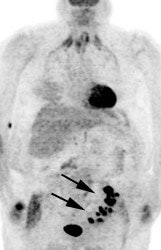

|

Genitourinary activity: The image below demonstrates activity within the collecting system of a transplanted kidney (black arrows). This should not be mistaken for an abnormality. |

|

|

|

Bladder cancer: Dilute urinary activity in this patient's bladder allowed accurate detection of their bladder cancer (white arrows on CT, black arrows on PET scan). In general, urinary excretion of FDG limits evaluation of urinary tract malignancies, however, hydration and diuresis can improve diagnostic accuracy. |

|

|